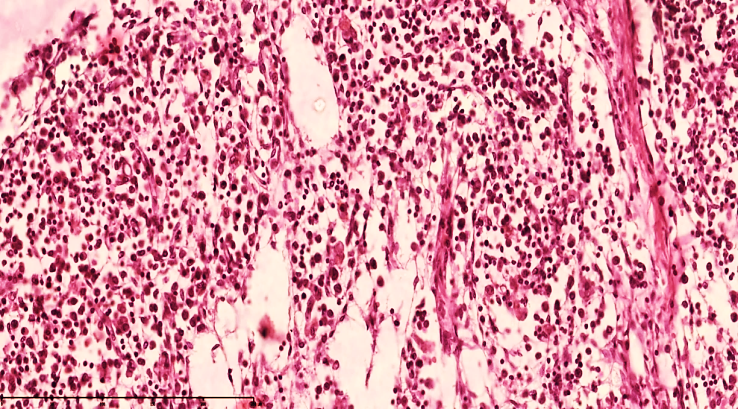

It was found that the main part of the regional lymph nodes is located in the ileocecal mandible and that massive enlargement of the lymph nodes occurs precisely in peritonitis. The lymph node capsule is tense, of uniform thickness, and reticulocytosis and macrophages are retained in the subcapsular space. As a result of the sharp increase in the level of fluid drainage, massively denuded stroma is detected in the lymphoid follicles in the active areas of the lymph node (cortical and paracortical areas) (see Figure 2). This indicates a connection with the massive recruitment of lymphocytes to the foci of inflammation. As a result, the lymph node acquires a swollen appearance, and loose lymph nodes are detected. The appearance of lymphoid follicles is sharply blurred against the general background, the follicle texture is lost, and neutrophils are detected around the postcapillary venules in the paracortical area. (see Figure 3). The abundance of mast cells confirms the acute course of the inflammatory process. | Figure 2. Mesenteric lymph node of a 28-day-old infant with peritonitis. The capsule is thickened, the subcapsular space is markedly enlarged, the peritrabecular areas are bare, formed in the form of a cavity, and the lymphoid follicles do not have a clear border. Staining G.E. Size 10x10 |

| Figure 3. Mesenteric lymph node of a 28-day-old infant with peritonitis. Macrophages are increased in the peritrabecular area, lymphocytes are decreased, and oligonucleated lymphoblasts are increased, and stroma is disrupted. Staining G.E. Size 40x10 |